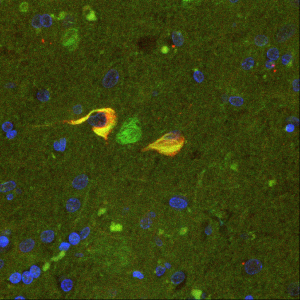

Κυραργύρη Βασιλική, Επιστημονικός Υπεύθυνος του ερευνητικού έργου με τίτλο: «Ο ρόλος της μικρογλοίας στην παθολογία και μεταβολή της επιτήρησης του εγκεφάλου κατά την απομυελίνωση»

Η νευροφλεγμονή είναι κοινό χαρακτηριστικό όλων των νευροεκφυλιστικών διαταραχών, από τις κατά βάση αυτοάνοσες όπως η Σκλήρυνση Κατά Πλάκας μέχρι τις κλασικές νευροεκφυλιστικές όπως η νόσος Alzheimer, και αποτελεί υποσχόμενο θεραπευτικό στόχο. Η μικρογλοία είναι τα τοπικά ανοσοποιητικά κύτταρα του κεντρικού νευρικού συστήματος (ΚΝΣ) που μεσολαβούν την εγγενή νευροφλεγμονή. Η χρόνια ενεργοποίησή τους προάγει την νευροφλεγμονή και επάγει την δευτερογενή αλλοίωση του εγκεφαλικού ιστού. Ωστόσο, πρόσφατα ερευνητικά δεδομένα έχουν δείξει ότι η μικρογλοία επιτελεί εξίσου σημαντικές ρυθμιστικές λειτουργίες στον υγιή εγκέφαλο, και έχει ευεργετικό ρόλο στην αποκατάσταση τοπικών αλλοιώσεων σε περίπτωση ασθενειών.